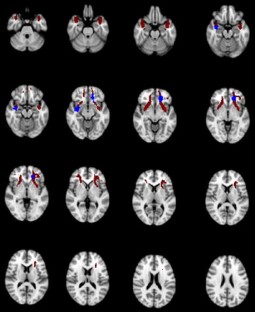

Recent evidence points to white-matter abnormalities as a key factor in autism physiopathology. Using Diffusion Tensor Imaging, we studied white-matter structural properties in a convenience sample of twenty-two subjects with low-functioning autism exposed to long-term augmentative and alternative communication, combined with sessions of cognitive and behavioral therapy. Uncinate fasciculus structural properties correlated significantly with therapy length and early onset, as well as to clinical outcome, independently from IQ, age or symptoms severity at therapy onset. Moreover, adherence to therapy was linked with better clinical outcome and uncinate fasciculus structural integrity. The results point to the capability of a long-term rehabilitation of subjects with low-functioning autism to produce white-matter structural modifications, which could thus play a role in the rehabilitative outcome.